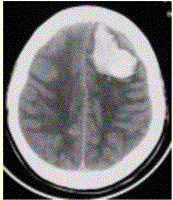

问题 患者男,45岁,突发剧烈头痛伴呕吐30min。既往有高血压病史,平日血压为(190~160)/(100~110)mmHg。查体:右侧肢体肌力Ⅱ级,无颈项强直。CT表现如下图。 请提出初步诊断

选项 A.急性脑梗死 B.急性脑血肿 C.蛛网膜下腔出血 D.脑星形细胞瘤 E.急性化脓性脑炎

答案 B